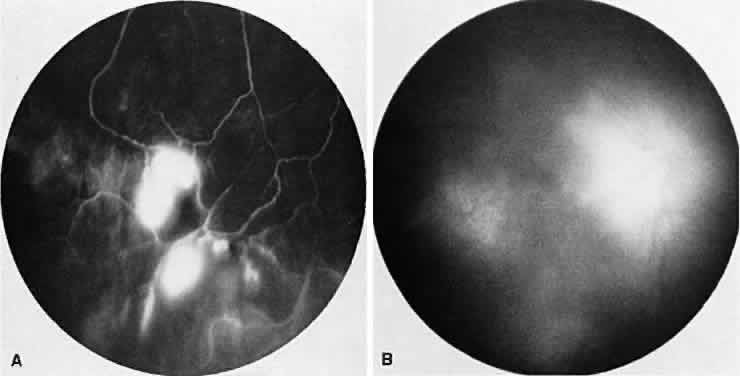

BIRDSHOT RETINOCHOROIDOPATHY

Birdshot retinochoroidopathy (also known as vitiliginous chorioretinitis) presents bilaterally, generally in middle-aged women, causing floaters and decreased vision, night blindness, and color blindness. Clinically, there are patches of postequatorial choroidal and retinal pigment epithelial depigmentation (Fig. 10A), vitreous cells, macular and disc edema, and venous sheathing. SRNV frequently is a late sequela. Often central vision may be preserved in at least one eye.

Fig. 10. Birdshot retinochoroidopathy. A. Multiple cream-color deep choroidal lesions. B. Fluorescein angiogram shows leakage of the optic disc and the retinal vasculature. C. Indocyanine green angiography showing areas of hypofluorescence that exceed those observed on fluorescein angiography.

On fluorescein angiography, retinal vessel staining, disc leakage, and cystoid macular edema are found (see Fig. 10B). There often is generalized hypofluorescence of the retinal vessels and increased circulation time.35,36 Surprisingly, the patches of depigmentation may appear normal on angiography, although there can be mild late hyperfluorescence.35,36 Posterior pole choroidal hyperfluorescent lesions that correspond to the areas of depigmentation and SRNV also can be seen.37

On ICG angiography (see Fig. 10C), early and late hypofluorescent patches, exceeding the clinically detectable lesions, with a choroidal vasotropic distribution and relative sparing of the peripapillary area and the central macula, are noted. These findings differentiate this condition from AMPPPE, multifocal choroiditis, and other granulomatous conditions such as sarcoidosis and sympathetic ophthalmia. Rarely, hyperfluorescent spots are noted in the late phases of the angiogram, which correspond ophthalmoscopically to retinal inflammation or obstructive changes.38